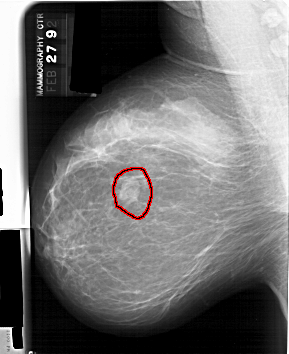

A_1389_1.LEFT_MLO

LEFT_MLO LINES 6361 PIXELS_PER_LINE 5191 BITS_PER_PIXEL 12 RESOLUTION 43.5 OVERLAY

FILE: A_1389_1.LEFT_MLO.OVERLAY

TOTAL_ABNORMALITIES 1

ABNORMALITY 1

LESION_TYPE MASS SHAPE LOBULATED MARGINS CIRCUMSCRIBED

ASSESSMENT 4

SUBTLETY 5

PATHOLOGY BENIGN

TOTAL_OUTLINES 1

BOUNDARY